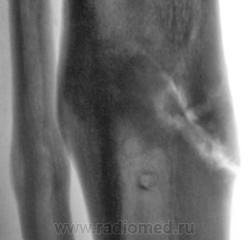

Щелевидный дефект до 1/2 d кости обусловлен, по всей вероятности, необезыствленной остеоидной тканью. Со временем "захряснет". Клиницисты в таких случаях констатируют консолидированный перелом.

СОСТОЯНИЕ КОСТНЫХ ОТЛОМКОВ УДОВЛЕТВОРИТЕЛЬНОЕ. ЛИНИЯ ПЕРЕЛОМА НЕ ОПРЕДЕЛЯЕТСЯ. ИЗБЫТОЧНАЯ КОСТНАЯ МАЗОЛЬ. А ДЛЯ ЧЕГО МСЭК?

Пациент борется "за группу" применяя все тактические дозволенные и не дозволенные действия. На мой взгляд , некоторая избыточная костная мозоль есть. Длинник кости сохранен.

Консолидированный  перелом костей голени на границе верхней и средней 1\3 диафизов. Состояние костных отломков удовлетворительное. Линия перелома, практически, не визуализируется. В б\б кости линия простветления до 1\2 поперечника, обусловленная дефектом костной ткан. Определяется избыточная костная мозоль. В верхней и средней 1\3 дефекты костной ткани как следствие перенесенной операции МОС. А на основании чего этот упорный пациент надеется получить группу?!  Все сопоставлено, срослось...  ???

Линия перелома хорошо видна на боковом снимке

Видна линия «просветения», в которой содержание солей кальция понижено. Но она не является линией перелома и пересекает не весь поперечник утолщенного диафиза. Главное: опорная функция восстановлена?